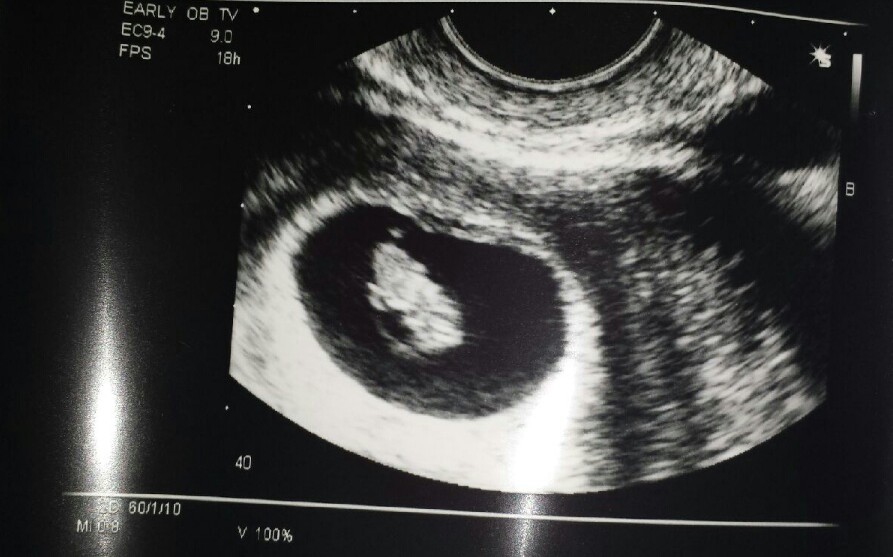

I have a couple of moments in my life that my anxiety level has been as high as it was yesterday. I knew I was going to get to see how big you’ve grown since our first ultrasound, and was also hoping to get the “okay” from Dr. B to tell the world that you were going to be joining us soon. Clammy hands, splotchy chest, and I wasn’t really sure if I could puke or pee my pants-all at the same…time…